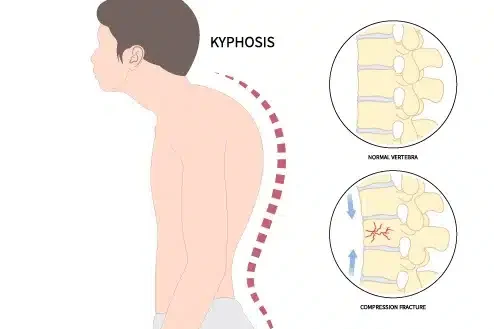

رابعًا: ما هو تقوس الظهر (الحداب)؟

تقوس الظهر هو انحناء للأمام في الجزء العلوي من العمود الفقري. في الحقيقة، هذا الانحناء طبيعي بدرجة معينة، لكن المشكلة تظهر عندما يزيد عن الحد الطبيعي.

📌 في الحالات الشديدة، قد يبدو الظهر:

- مستديرًا بشكل واضح

- مع ميل الرأس للأمام

- وانحناء في الكتفين

👉 وبالتالي، قد يؤثر على الشكل العام والثقة بالنفس.

خامسًا: ما أسباب تقوس الظهر؟

📌 2. هشاشة العظام

تحدث غالبًا عند كبار السن وتؤدي إلى ضعف الفقرات.

📌 3. الإصابات

مثل كسور الفقرات نتيجة الحوادث.

📌 4. مرض شويرمان

وهو نوع يظهر في المراهقين بسبب تشوه في نمو الفقرات.

👉 لذلك، يختلف العلاج حسب السبب وشدة الحالة.